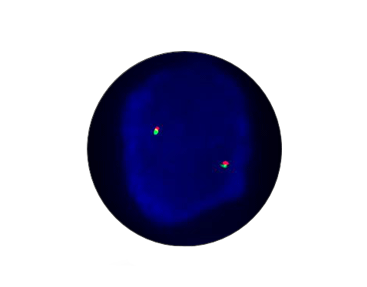

EWSR1 Breakapart

Probe Description: EWSR1

Cat.No.: CF1070